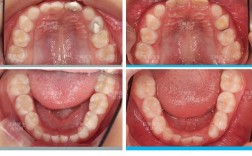

患者:小明(化名),男,7岁6个月主诉:家长发现孩子上前牙咬在下前牙舌侧,影响美观和咀嚼,就诊时间:混合牙列早期(乳牙列即将结束,恒前牙开始萌出),临床检查与诊断口外检查:面型:面下1/3略显凹陷,下颌前突,颏部前突,上唇后缩,鼻...